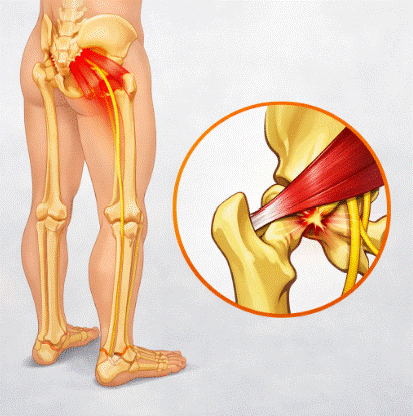

Parálisis del nervio peroneo: causas, diagnóstico y tratamiento

La parálisis del nervio peroneo es la neuropatía compresiva más frecuente del miembro inferior, y sin embargo sigue siendo una de las entidades más infradiagnosticadas en la consulta de fisioterapia y neurología. Su manifestación más característica, el pie caído, genera una alteración del patrón de marcha que aumenta significativamente el riesgo de caídas y compromete […]